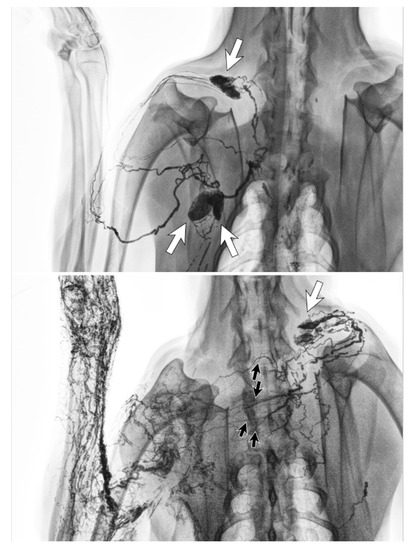

3.1. Dermal Backflow

- Suami, H.; Pan, W.-R.; Taylor, G.I. Changes in the Lymph Structure of the Upper Limb after Axillary Dissection: Radiographic and Anatomical Study in a Human Cadaver. Plast. Reconstr. Surg. 2007, 120, 982–991. [Google Scholar] [CrossRef]

- Suami, H.; Pan, W.-R.; I Taylor, G. The lymphatics of the skin filled by a dermal backflow: An observation in a scarred cadaver leg. Lymphology 2007, 40, 122–126. [Google Scholar]

- Suami, H.; Koelmeyer, L.A.; Mackie, H.; Boyages, J. Patterns of lymphatic drainage after axillary node dissection impact arm lymphoedema severity: A review of animal and clinical imaging studies. Surg. Oncol. 2018, 27, 743–750. [Google Scholar] [CrossRef]